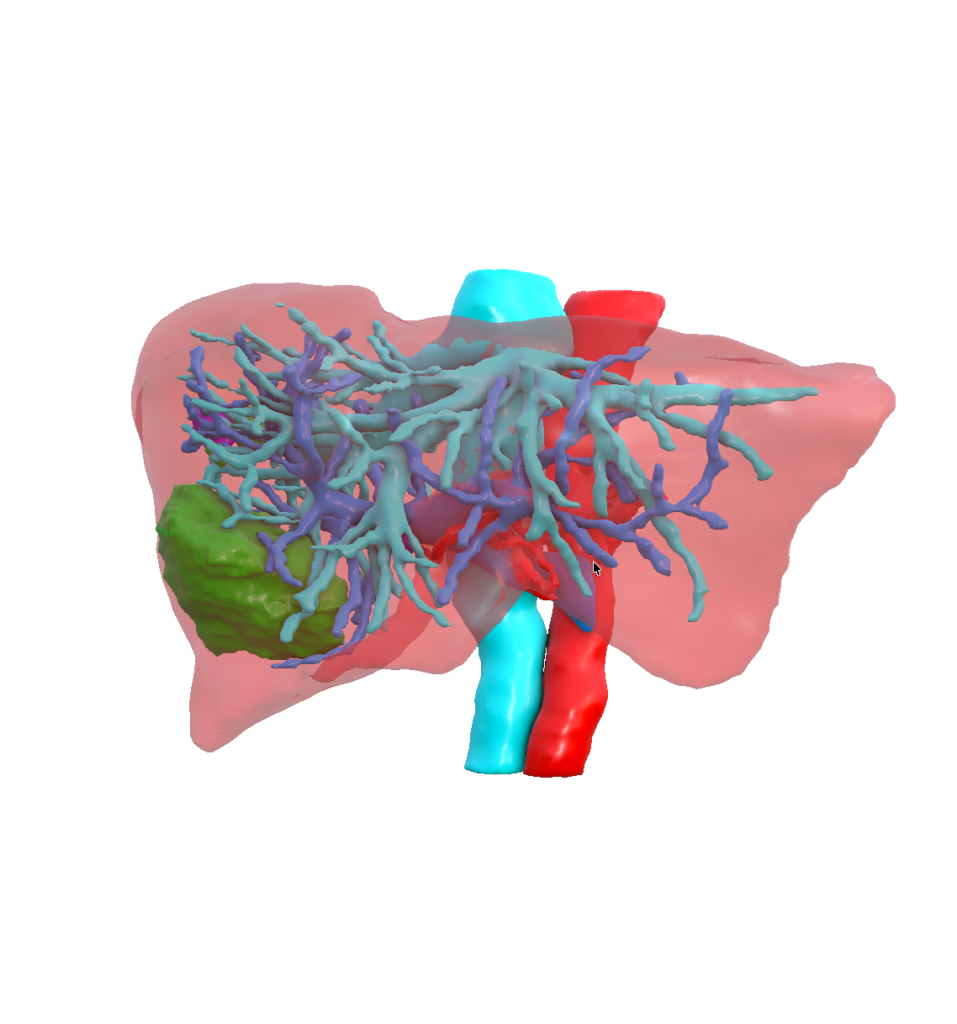

Our mission is to unlock the full potential of medical imaging data by transforming clinically validated CT and MRI images into high‑fidelity, synthetic digital human twins—enabling trustworthy, scalable, and privacy‑preserving AI development for healthcare.

To extend Visible Patient Lab’s clinically validated 3D anatomical expertise into synthetic digital human twins, enabling safe and effective AI innovation without compromising medical accuracy or patient privacy.